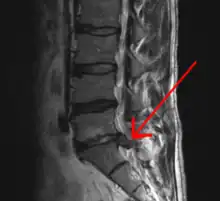

Imaging is indicated when there are red flags, ongoing neurological symptoms that do not resolve, or ongoing or worsening pain.[5] In particular, early use of imaging (either MRI or CT) is recommended for suspected cancer, infection, or cauda equina syndrome.[5] MRI is slightly better than CT for identifying disc disease; the two technologies are equally useful for diagnosing spinal stenosis.[5] Only a few physical diagnostic tests are helpful.[5] The straight leg raise test is almost always positive in those with disc herniation,[5] and lumbar provocative discography may be useful to identify a specific disc causing pain in those with chronic high levels of low back pain.[47] Therapeutic procedures such as nerve blocks can also be used to determine a specific source of pain.[5] Some evidence supports the use of facet joint injections, transforminal epidural injections and sacroiliac injections as diagnostic tests.[5] Most other physical tests, such as evaluating for scoliosis, muscle weakness or wasting, and impaired reflexes, are of little use.[5]